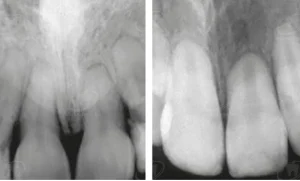

– Dấu hiệu nhận biết: Bệnh thường không gây đau nên rất khó tự phát hiện. Đôi khi, bạn có thể thấy một đốm hồng trên thân răng (gọi là “răng hồng”) do mô tủy viêm đỏ xuyên thấu qua lớp men mỏng. Đa số các trường hợp chỉ được phát hiện tình cờ khi chụp phim X-quang nha khoa.

- Thăm khám định kỳ: Chụp phim X-quang là cách duy nhất để phát hiện sớm các vùng tiêu ngót trước khi chúng gây ra triệu chứng.